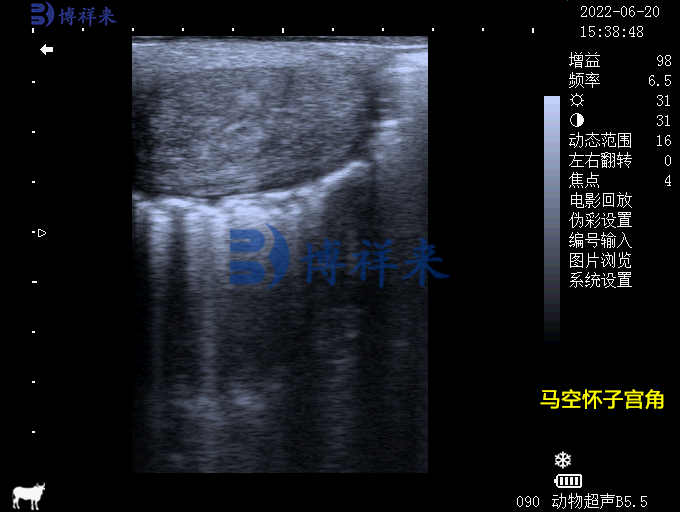

马空怀子宫角

【子宫角(发情期)的横截面:液体潴留和子宫皱襞的轮状外观】